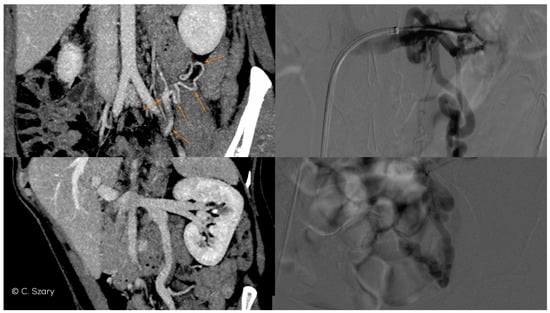

4.2. Grading of Ovarian Veins Insufficiency

4.2.2. Grade I/II (GI/II)

4.2.3. Grade II (GII)